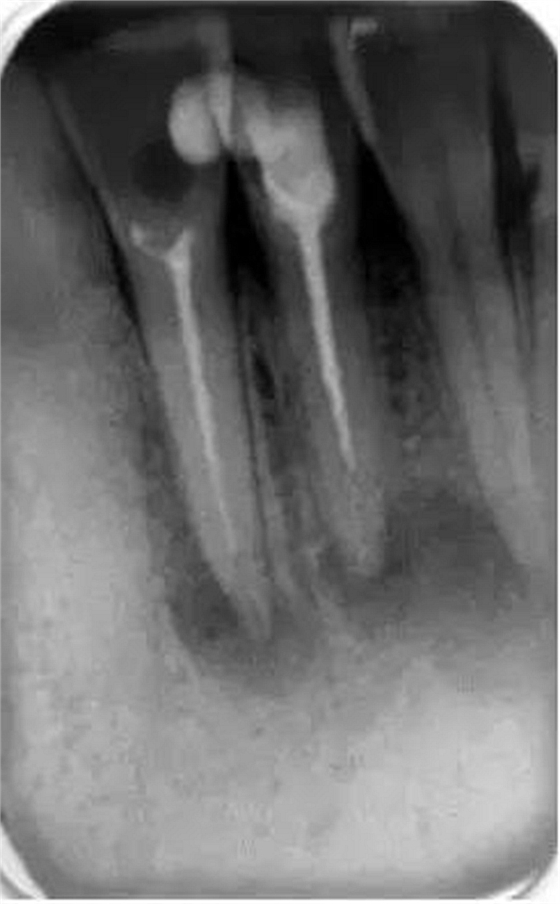

它還有助于臨床醫(yī)生決定他是否有能力進(jìn)行該病例的治療還是應(yīng)該將患者轉(zhuǎn)診到專科醫(yī)生處進(jìn)行治療。還可以在治療前明確髓腔內(nèi)是否有髓石以及牙齒或根管內(nèi)是否有其他阻塞物(如樁、釘、分離的儀器或根填充材料)(圖2)。這是很重要的,因?yàn)樗鼤?huì)給臨床醫(yī)生一些預(yù)后和治療中可能出現(xiàn)的一些問(wèn)題的提示。所有這些因素必須在治療前與患者進(jìn)行溝通,以便其決定是否要繼續(xù)進(jìn)行根管治療。